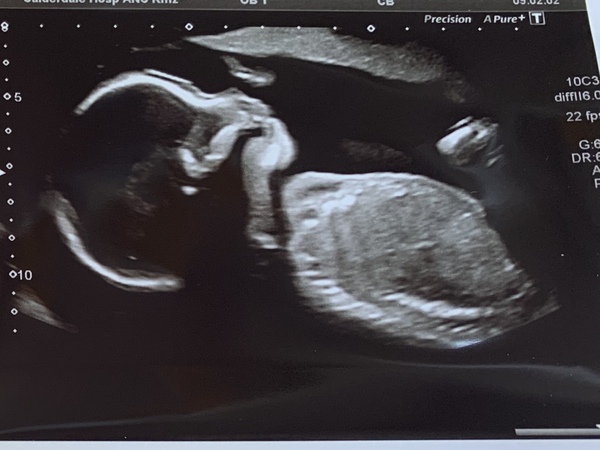

bobble53 · 18/07/2019 17:33

My scan :)

Due December 2019- continued